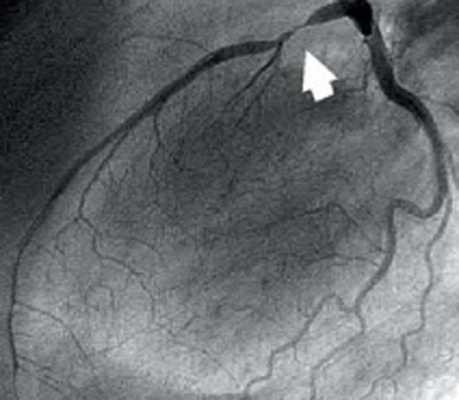

При селективной коронарографии (26.08.2009 г.) левая венечная артерия (ЛВА) не обнаружена в ее типичном месте - ЛКС. При катетеризации ПВА выявлено аномальное отхождение СЛВА от ПКС отдельным стволом. Проксимальная часть СЛВА проходила между аортой сзади и легочным стволом спереди, дальше переходя на переднюю стенку левого желудочка. В бассейне ЛВА наблюдали обнаружен эксцентрический стеноз передней межжелудочковой ветви (ПМЖВ) ЛВА в проксимальной трети - 80 %. В бассейнеПВА - внутристентовый рестеноз в средней трети - 70 % и стеноз в проксимальной трети ПВА - 50 %.

В одну сессию с коронаровентрикулографией, больному было проведено стентирование ПМЖВ ЛВА, был имплантирован элютинг-стент (Cypher, Cordis, J&J, США) длиной 33 мм на баллоне-катетере диаметром 2,75 мм и под давлением в баллоне 14 атм. Непосредственный ангиографический результат был хорошим. Магистральный кровоток в бассейне ЛВА был восстановлен полностью.